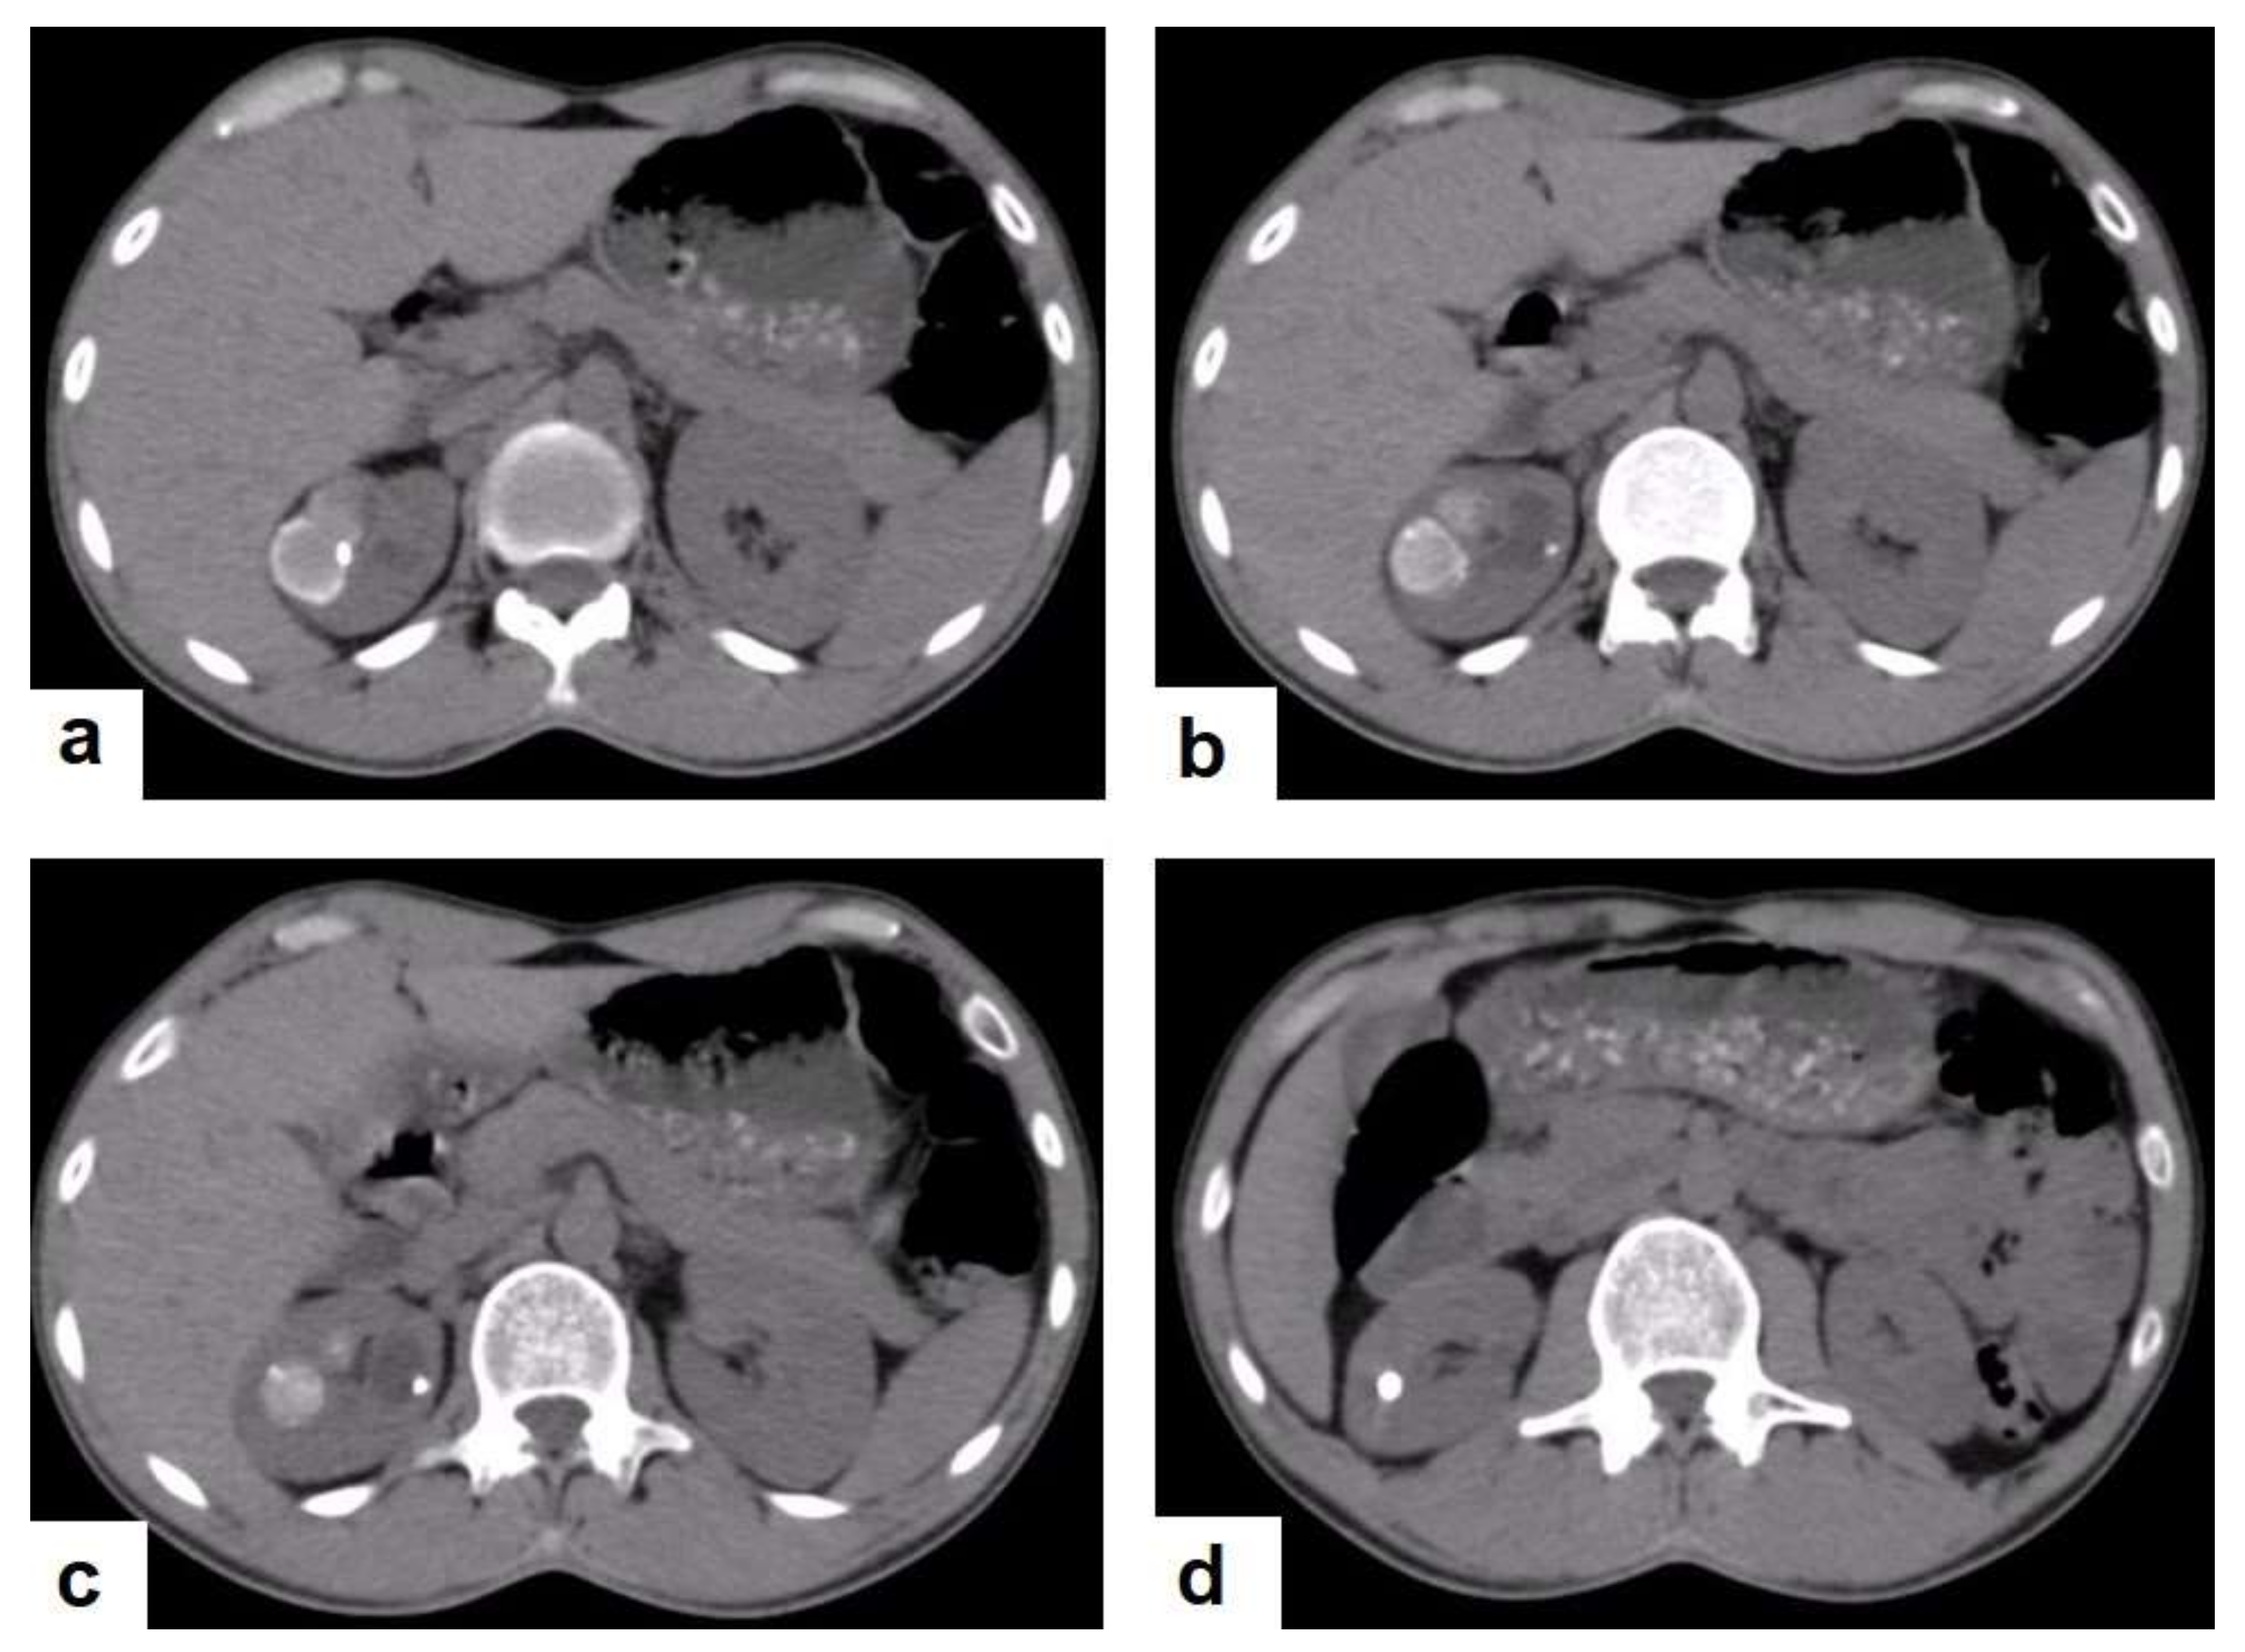

Figure 23. Renal TB in a 39-year-old man. Selected axial computed tomography images show (a) focal hyperdense non-enhancing nodules, with the largest at 26 mm, with calcified rim in the upper pole of the right kidney with focal scarring of the kidney. (b,c) Approximately, 20 mm cystic lesion in the upper calyx with focal calcification, most likely dilated calyx; and (d) 11 mm focal parenchymal calcification in the middle calyx.

Radiological features of renal TB are varied and depend on the stage of a TB infection, which can present as pyelonephritis with total or partial swelling of the kidney, cortical scarring, cortical granulomas (Figure 23) and parenchymal calcifications (Figure 23d). TB infections of the collecting system vary from papillary necrosis at an early stage, and multifocal strictures, hydronephrosis, and dystrophic calcification to putty kidney (auto nephrectomy) at the kidney’s end-stage [54,55]. At each stage, renal TB can mimic other renal infections and even tumors. However, it can also be a differential diagnosis of renal cell carcinoma [56].